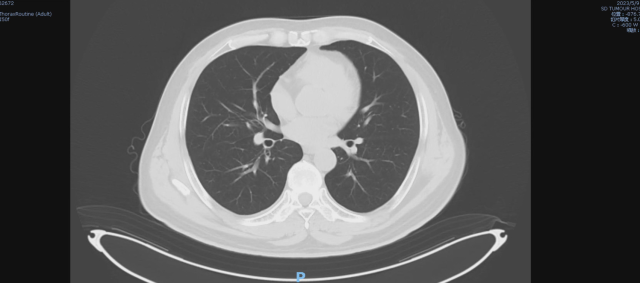

03 CT

1. 左肾及肾周占位,建议结合其他检查;2. 双肺多发小结节灶,结合病史,考虑转移;3. 双侧胸腔及心包腔少量积液;4. 前列腺钙化灶;5.L5 双侧椎弓崩解;6. L2 椎体致密灶,建议观察。